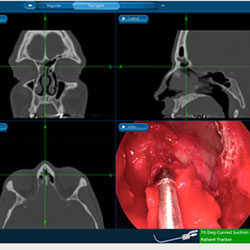

Both medical and surgical treatment options can be discussed, and if it is determined that you may benefit from revision sinus surgery, our surgeons will use the latest techniques to safely correct the problem and restore health to your sinuses.